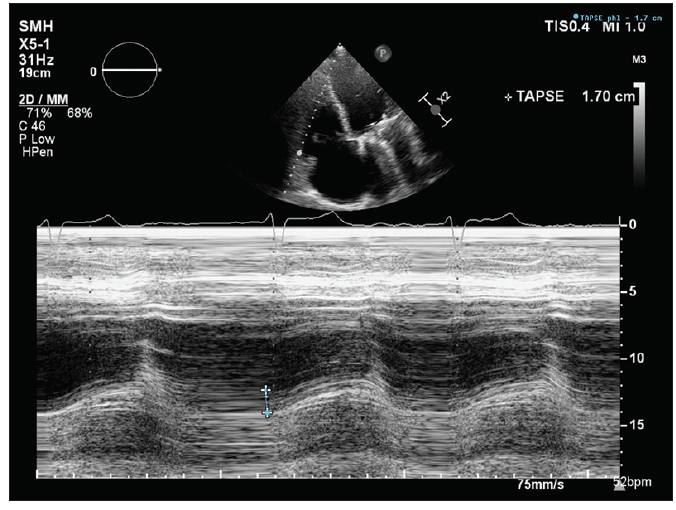

The patient’s left ventricular (LV) systolic function was mildly reduced (LV ejection fraction, 40%–45%), and he had a dilated right ventricle with mild systolic dysfunction based on standard normal ranges (Figure 1 and Figure 2). His right ventricular (RV) systolic pressure was estimated to be 56 mm Hg, as assessed by echocardiography. The results of right heart catheterization showed a pulmonary capillary wedge pressure of 19 mm Hg (V wave to 28 mm Hg), pulmonary artery pressure of 50/14 mm Hg (mean, 29 mm Hg), RV pressure of 50/14 mm Hg, and right atrial pressure of 15 mm Hg (V wave to 20 mm Hg).

Dr. Hahn: Multiple modalities can be used to assess RV size and function (CT, cardiovascular magnetic resonance, echocardiography), with recent studies suggesting that RV strain (either by echocardiography or cardiovascular magnetic resonance) can possibly predict outcomes. In truth, we don’t know the best way to assess RV plasticity and its ability to recover. Evaluation of RV–pulmonary artery coupling may also play a role. On echocardiography, tricuspid annular plane systolic excursion, fractional area change, and tissue Doppler S´ are the easiest to measure; however, free wall strain (or global longitudinal strain including the septum) may be superior to these methods.